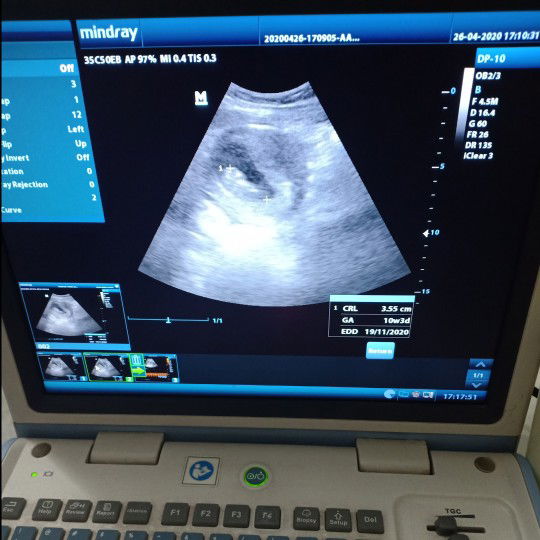

hpht dan usg selisih

Hasil usg uk 10w 3d tp klo ikutin hpht uk 11w 5d jadi selisih 1 mingguan tp alhamdulilah janin aktip udh gerak gerak dan ddj normal, saya bingung mau 4bulanan kira kira menurut bunda ikutin itungan hpht atau ikutin usg karna beda semingguan?